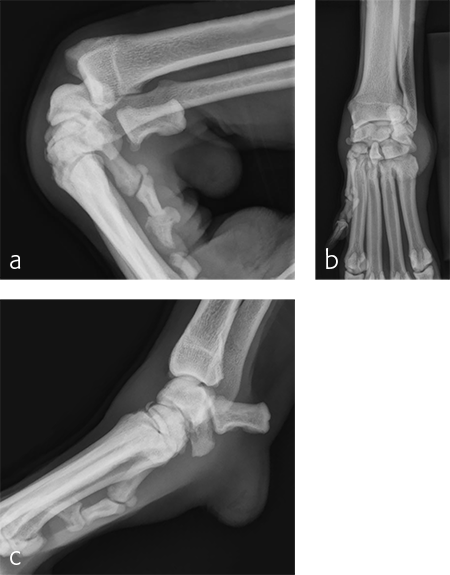

A 5-year-old neutered male Labrador Retriever weighing 24.6 kg presented with a right forelimb lameness of 4-month duration. The lameness occurred acutely and the dog was initially nonweight-bearing. The cause of the injury was not observed. Physical examination revealed a weight-bearing lameness of the right forelimb. The region of the right carpus was swollen compared to the left due to periarticular soft-tissue proliferation. A mild increase of synovial fluid and joint capsule distension was palpated. The right carpus was painful on extension and could be hyperextended to 30 degrees. The normal left carpus would extend to 10 degrees, which is the normal range of motion. Mild muscle atrophy of the right forelimb was observed. The neurological exam was normal. Radiographic examination revealed mild hyperextension, periarticular soft-tissue proliferation, and mild osteoarthritis (Fig 3). It was difficult to determine the joint level of instability of the right carpus based on the radiographic views. A diagnosis of hyperextension injury of the right carpus was made. The surgical plan included arthroscopic examination of the right carpus to assess the antebrachiocarpal joint to determine if it was affected, which would necessitate a pancarpal vs partial carpal arthrodesis.

A 7-year-old, 32.5 kg, Labrador Retriever became acutely lame on the left thoracic limb while catching a ball. It was evaluated three weeks later and had carpal swelling, pain, and instability of the left carpus. Flexed lateral, craniocaudal, and extended mediolateral view images of the left carpus revealed a dorsal chip fracture at the carpometacarpal joint and hyperextension of the left carpus (Fig 9).